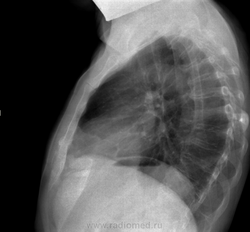

Пациент 1971 г.р., без каких либо жалоб.

Архив 2011 год

Вертикальная линейная палоса-вероятно не патология,тень мышцы.Очаговая тень слева в прикорневой зоне весьма нехороша,требуется уточнение.лучше КТ.Может оказаться опухолью.Поздравляем с дебютом.

Тень отмеченная на прямом снимке, на мой взгляд, тень сосуда, на боковом - передняя поверхность позвоночника (передняя продольная связка). А вот жалобы, скорее всего, есть. Грудная клетка бочкообразной формы - косвенный снимок бронхиальной обструкции.

Позвольте не согласиться с сосудом,уважаемый Андрей Юрьевич,форма тени овальная,не округлая,да и размеры великоваты для сосуда.

сделана на выдохе. Сосуд.

Неглубоко вдохнул, поэтому корни другой вид приобрели, я тоже за сосуд

Сосуд. На свежих снимках тени нету.

Завтра тогда попробую переделать в прямой проекции на максим. вдохе. А в позвонках нет ли компресии, Th7-Th8 единый костный блок?

Нет, не единый.

При таких изменениях в позвоночнике и нет жалоб? - сомнительно!